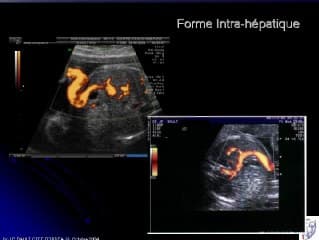

Après un rappel embryologique indispensable à la compréhension, JP BAULT nous explique comment diagnostiquer la persistance de la VO droite (et non gauche), qui est observée dans 1/500 cas.Devant cette situation il faut différentier les formes intra-hépatiques avec perméabilité du ductus venosus, des formes extra-hépatiques dans lesquelles on peut observer beaucoup plus de pathologies associées, dont le redoutable syndrome de Noonan. Un arbre décisionnel nous aide à y voir plus clair dans la CAT.